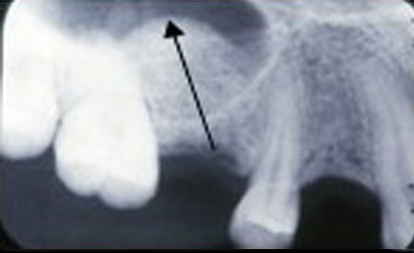

Dental implants are a suitable way to replace missing teeth. However, in some people, the dentist discovers through examination and photography that the jaw bone cannot support the implant.

For such people, sinus surgery is necessary. This procedure places the implant inside the jawbone more quickly, reducing complications after implantation.

For a sinus lift to be effective, sinus grafting is indispensable. This is a stage in a dental implant where the dentist positions or leverages bone or bone substitutes to the upper jaw near the sinuses.

The bone this graft creates fosters new bone growth that will allow dental implants to be securely positioned after the graft has fully integrated.